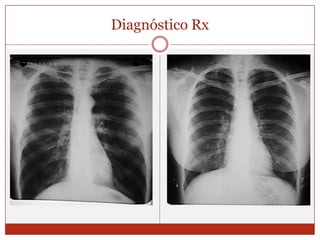

DIAGNOSTICOCuadro clínicoEspirometríaOximetriaRx de tórax

Diagnóstico Rx